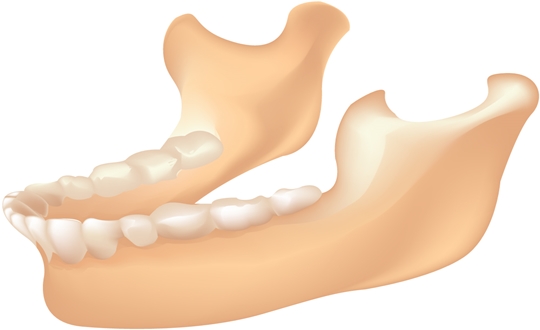

대화하거나 음식을 씹는 등 턱 운동을 담당하는 턱관절에는 머리뼈와 턱뼈 사이를 연결해주는 디스크가 있다. 여러 가지 원인으로 관절이 잘 맞지 않는 상태에서 이 디스크가 계속 움직이고, 밀리고, 압박받는 등 정상 위치에서 벗어나면 턱관절 장애 또는 턱 디스크가 생길 수 있다.